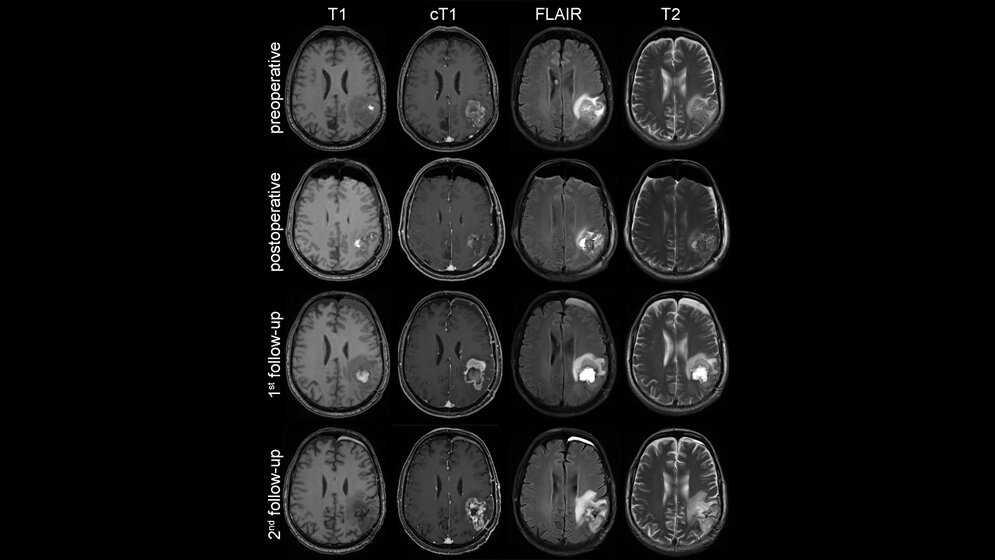

Anhand einer Referenzdatenbank mit MRT-Untersuchungen von knapp 500 Hirntumorpatienten des Universitätsklinikums Heidelberg erlernten die Algorithmen unter dem Einsatz künstlicher neuronaler Netzwerke die Hirntumoren automatisch zu erkennen und zu lokalisieren. Außerdem wurden die Algorithmen darauf trainiert, die einzelnen Bereiche (kontrastmittelaufnehmender Tumoranteil, peritumorales Ödem) volumetrisch zu vermessen und das Therapieansprechen präzise zu beurteilen.

Die Ergebnisse wurden in Kooperation mit der European Organisation for Research and Treatment of Cancer (EORTC) umfassend validiert. „Die Auswertung von über 2.000 MRT-Untersuchungen von 534 Glioblastom-Patienten aus ganz Europa zeigt, dass unser computerbasierter Ansatz eine zuverlässigere Beurteilung des Therapieansprechens ermöglicht, als es mit der herkömmlichen Methode der manuellen Messung möglich wäre. Wir konnten die Verlässlichkeit der Beurteilung um 36 Prozent verbessern. Das kann für die auf Bildgebung basierende Beurteilung der Wirksamkeit einer Therapie in klinischen Studien von entscheidender Bedeutung sein. Auch die Vorhersage des Gesamtüberlebens war mit unserem neuen Verfahren exakter möglich“, erklärt Kickingereder.